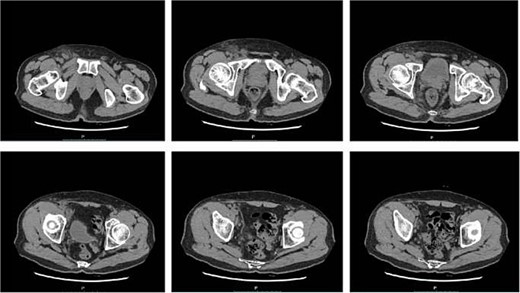

Empiric treatment with IV ampicillin and blood culture was initiated due to suspected lymph node inflammation. On Day 15, the patient’s symptoms worsened, with increased lymph node size to 2 × 4 cm, oral ulcers, and abdominal lesions. Labs showed leukocytosis with neutrophilia (white blood cells 10.74 × 109/L, neutrophil percentage 85.4%,) and elevated CRP (123.2 mg/L). Computed tomography (CT) scans revealed: (i) Local fibrous cord in the lower lobes of both lungs. (ii) Multiple small nodules in both lungs. (iii) Splenic enlargement. (iv) Possible inflammatory changes in the right pelvic and inguinal regions with multiple enlarged lymph nodes (Fig. 4).

CT scans revealed inflammatory changes and enlarged lymph nodes in the right pelvic and inguinal regions, leading to a diagnosis of fever due to inguinal lymphadenitis. The antibiotic treatment was intensified to include IV cefoperazone sodium, sulbactam sodium, and metronidazole.On postoperative Day 16, the patient had persistent fever (37.3°C–38.7°C) and symptoms, with normal rheumatoid factor and immune panel but elevated erythrocyte sedimentation rate (ESR) (53 mm/H), IL-6 (164.95 pg/ml), and CRP (153.2 mg/L),and white blood cells, procalcitonin (PCT) were normal. Despite IV sulbactam sodium and metronidazole, fever persisted on day 20 (37.3°C–39.2°C), with worsening symptoms. Blood cultures were negative. On the 22nd postoperative day, the pathological report indicated destruction of the lymph node structure with visible coagulative necrotic foci and focal necrosis of histiocytes, which was consistent with necrotizing lymphadenitis. The patient was started on oral prednisone acetate (15 mg three times a day). After 5 days of treatment, the patient’s body temperature gradually returned to normal, the pain in the right inguinal lymph node subsided, its size decreased to 2 × 2 cm, the oral ulcers began to heal, and the abdominal papules and pustules resolved (Fig. 5).